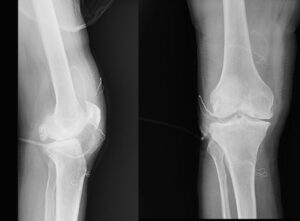

Diz ağrısı şikâyeti ile geldiği Düzce Üniversitesi Tıp Fakültesi Hastanesi’nde ameliyata alınan hastanın dizlerinden toplam 41 adet multipl sinovial kondromatozisi çıkartıldı. Özellikle diz eklemi çevresinde görülmekle birlikte kalça, dirsek ve diğer eklemlerde de görülen, ufak parçalardan oluşan cisimler olarak tanımlanan eklem faresi, eklem çevresinde eklem sıvısı ya da sinoviyumda görülen kıkırdak ya da kemik parçalarıdır. Eklem farelerinin boyutları birkaç milimetreden birkaç santimetreye kadar çıkabiliyor.